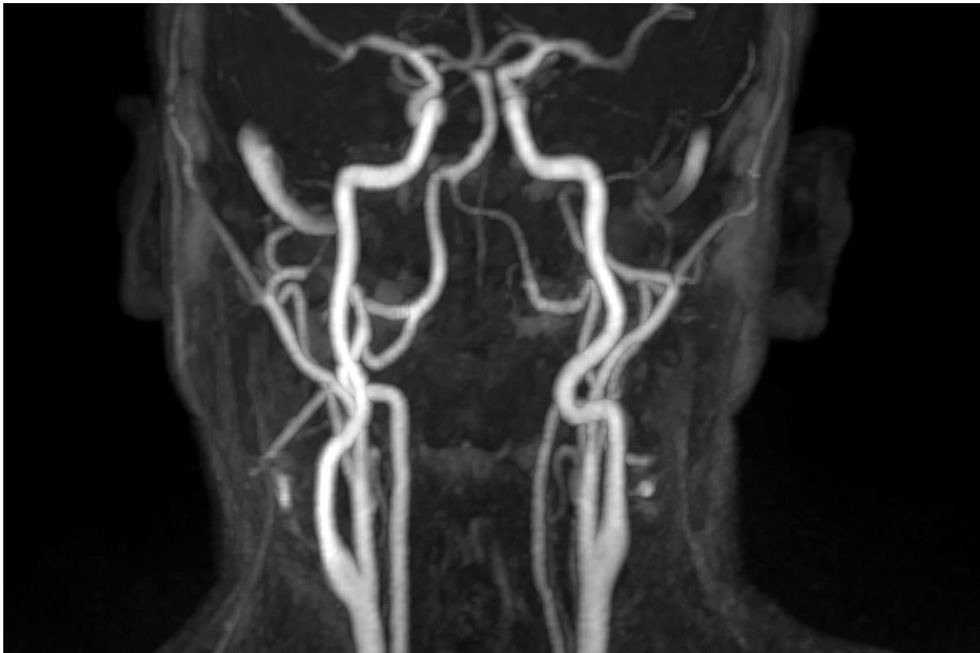

“Higher circulating calcium levels within the normal range are associated with increased thickness in the major arteries going to your brain and a higher prevalence of abdominal aortic calcification, and more calcified plaques in the coronary arteries,” she said.